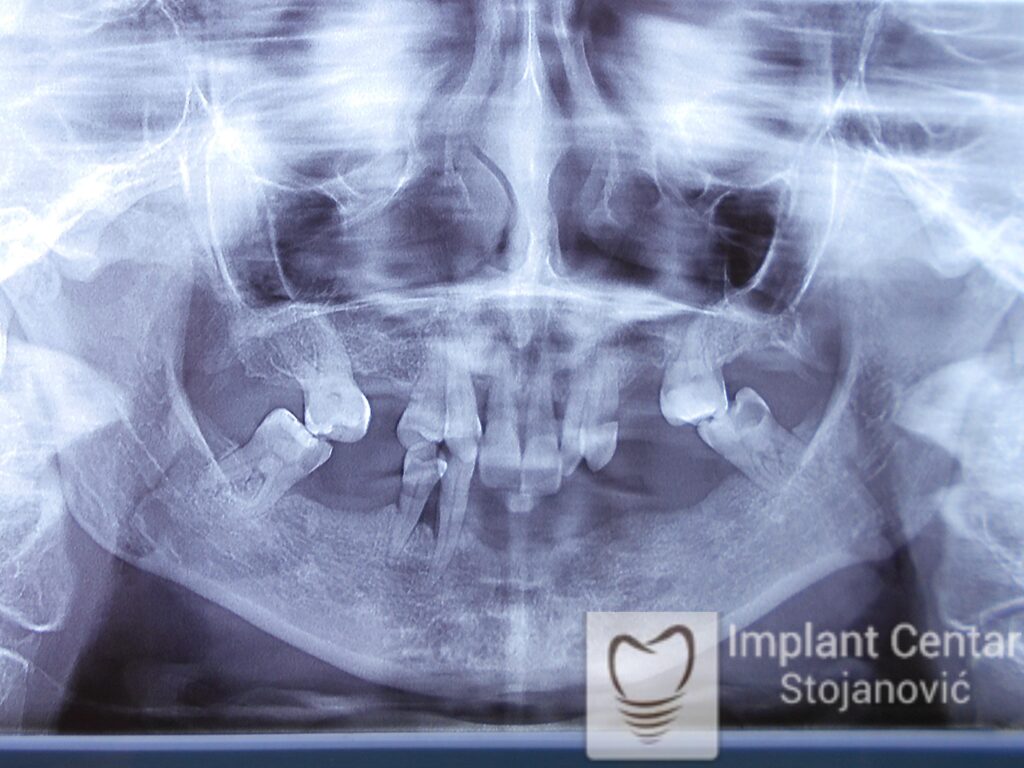

Na slici 1. i slici 2. prikazan je izgled pacijenta pre početka terapije – klinički i rendgenološki.

Nakon vađenja zuba, ugrađeni su implantati. Na slici 3 prikazan je ortopan snimak sa ugrđenim implantatima. Tokom perioda osteointegracije, pacijent je bio zbrinut fiksnim privremenim krunicama na implantatima, koje su izrađene samo dva dana nakon hirurške intervencije.

Na slikama 5. i 6. prikazan je izgled definitivnih cirkonijum-keramičkih mostova na implantatima.